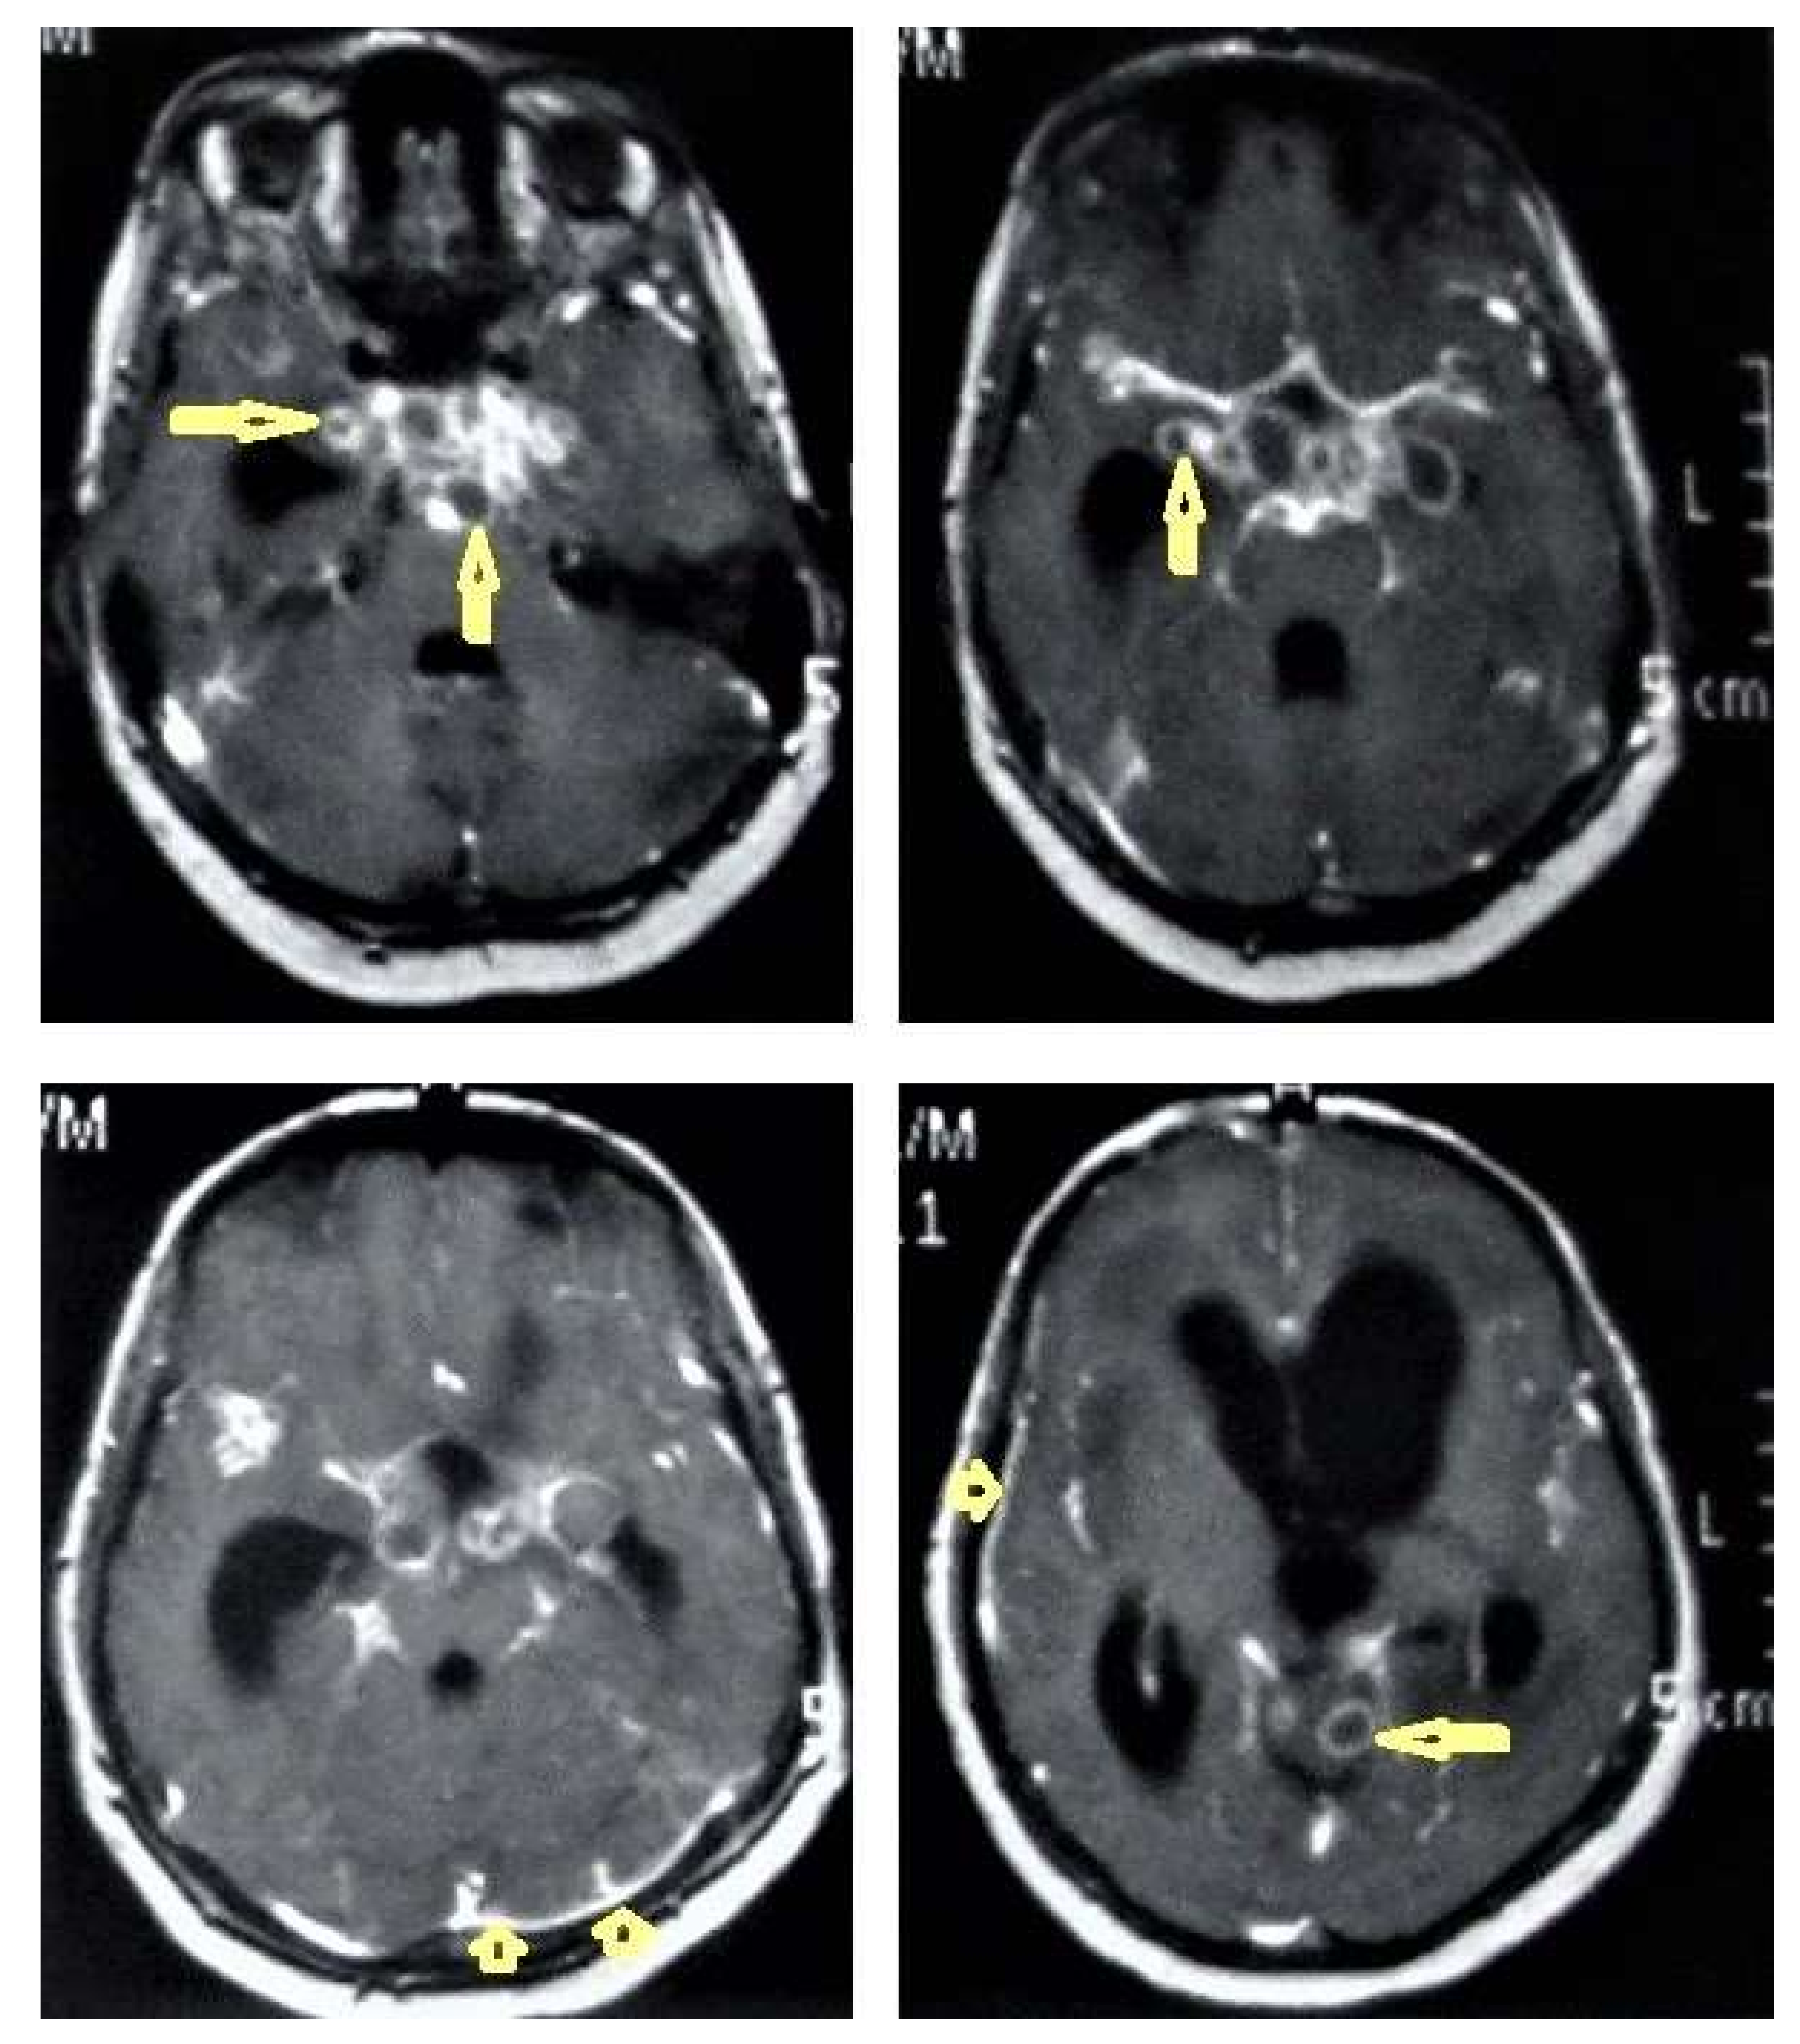

• Tuberculoma (Tuberculous granuloma; Figure 12 and Figure 13) is one of the most common brain parenchymal tuberculous lesions and can be solitary or multiple anywhere within the brain. It is commonly seen at the corticomedullary junction and periventricular region as a result of hematogenous dissemination. MRI features of tuberculoma vary according the stage of maturation (stage 1, non-caseating; stage-2, caseating granuloma; stage 3, caseating granuloma with central liquefaction; and stage 4, calcified granuloma). Radiologically, each stage of brain tuberculoma can mimic a wide variety of differential diagnoses, such as neurocysticercosis, fungal granulomas, pyogenic abscess, metastasis, glioma, lymphoma, and toxoplasmosis [25,27]. Ring-enhancing lesions of the brain may form a diagnostic dilemma [30].

• Miliary tuberculomas (Figure 13) occur due to the haematogenous dissemination of Mycobacterium tuberculosis bacilli, which are usually lung focused and occur especially in immunocompromised patients. They appear as innumerable small (2–3 mm) non-caseating granulomas with random distribution in the brain with a predominance to a gray-white matter junction as a result of hematogenous dissemination [25,26]. Miliary TB usually strongly mimics brain metastasis [31].

Figure 13. Multiple tuberculomas in an adult man. Selected MRI axial images post-contrast T1-weighted images show multiple small ring-enhancing lesions distributed in both cerebral hemispheres, with no significant surrounding cerebral edema, as is consistent with cerebral tuberculomas.